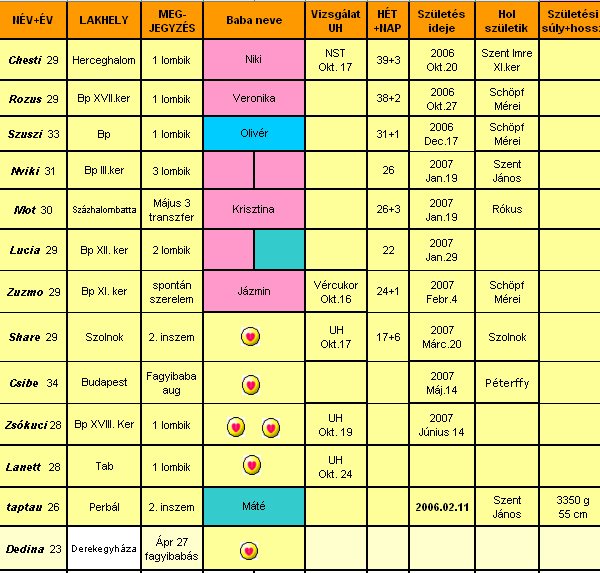

Tegnap UH vegyes érzésekkel telt. Luca/Máté teljesen egészséges végtagilag és belszervileg is. Méretei megfelelőek.

Viszont nálunk az a legújabb, hogy a 18. és a 20. héten is van uh, és két különböző orvosnak kell néznie. Megbeszéltük a dokimmal, hogy a 18. heteset más csinálja majd. Tegnap egy profi uh-s doki volt, még örültem is. Nadehát a modora!!!????? Tudtam, hogy fapofa, de évek óta nem találkoztam vele. Először is nem jöhetett be a férjem. Másodszor én sem láthattam a babát. Harmadszor még le is tolt, hogy korán jöttem, később jobban lehet látni, ha gond van. Nehát kinyílt a bicska a zsebemben! Közöltem vele, hogy a 20. héten is kell jönni, akkor most éppen jókor vagyok itt. Erre azt mondta, hogy hülyeség, majd úgyis megváltoztatják. Dilííís!